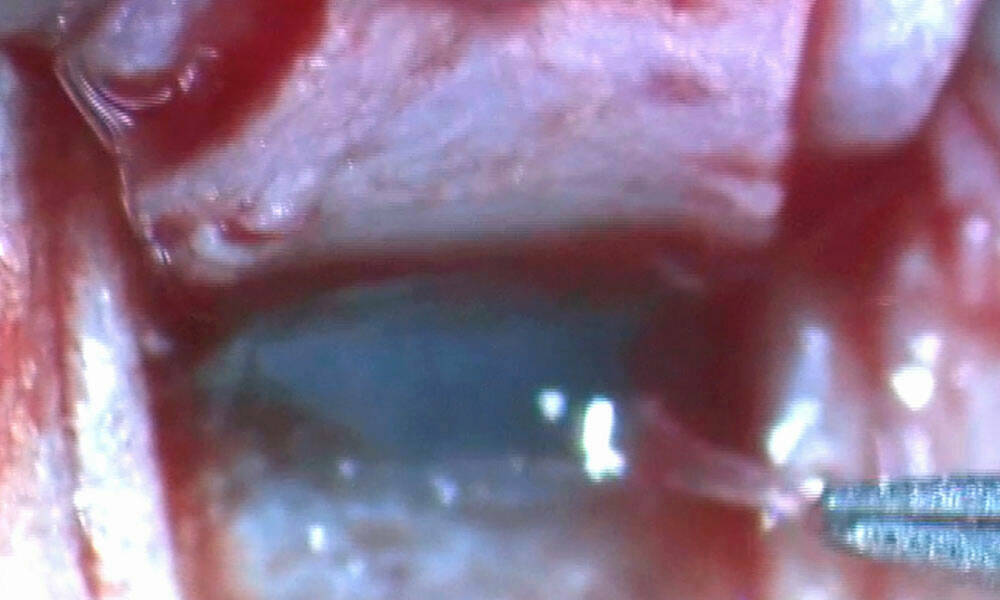

Figure 2. Examen à la lampe à fente avec la LRPG Menicon Rose K2 PG. À gauche : Examen lumière blanche : LRPG en position supérieure, corectopie et atrophie irienne en rapport avec le syndrome ICE. À droite : Examen à la fluorescéine après adaptation ; la lentille est prescrite à l’essai.